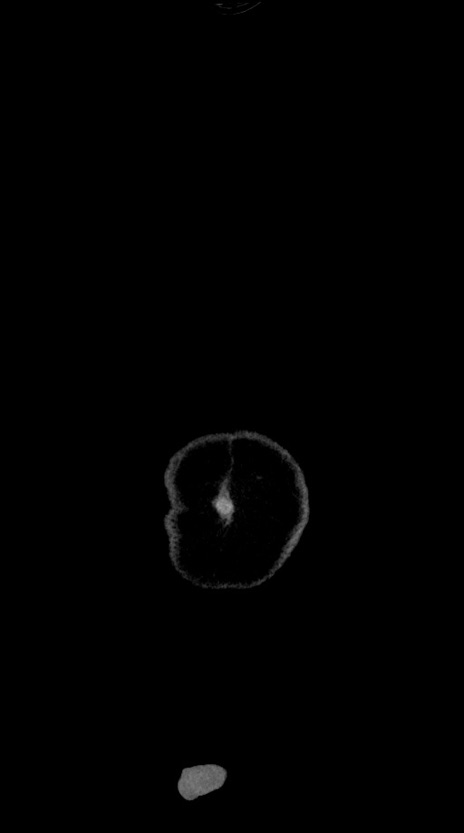

横断像

【症例】60歳代男性

【主訴】嘔吐

【現病歴】胃癌にて胃全摘後。食思不振が悪化し、夜中に嘔吐することがある。

【既往歴】胃癌、胃全摘、脾摘、胆摘後

【データ】WBC 5900、CRP 10.56